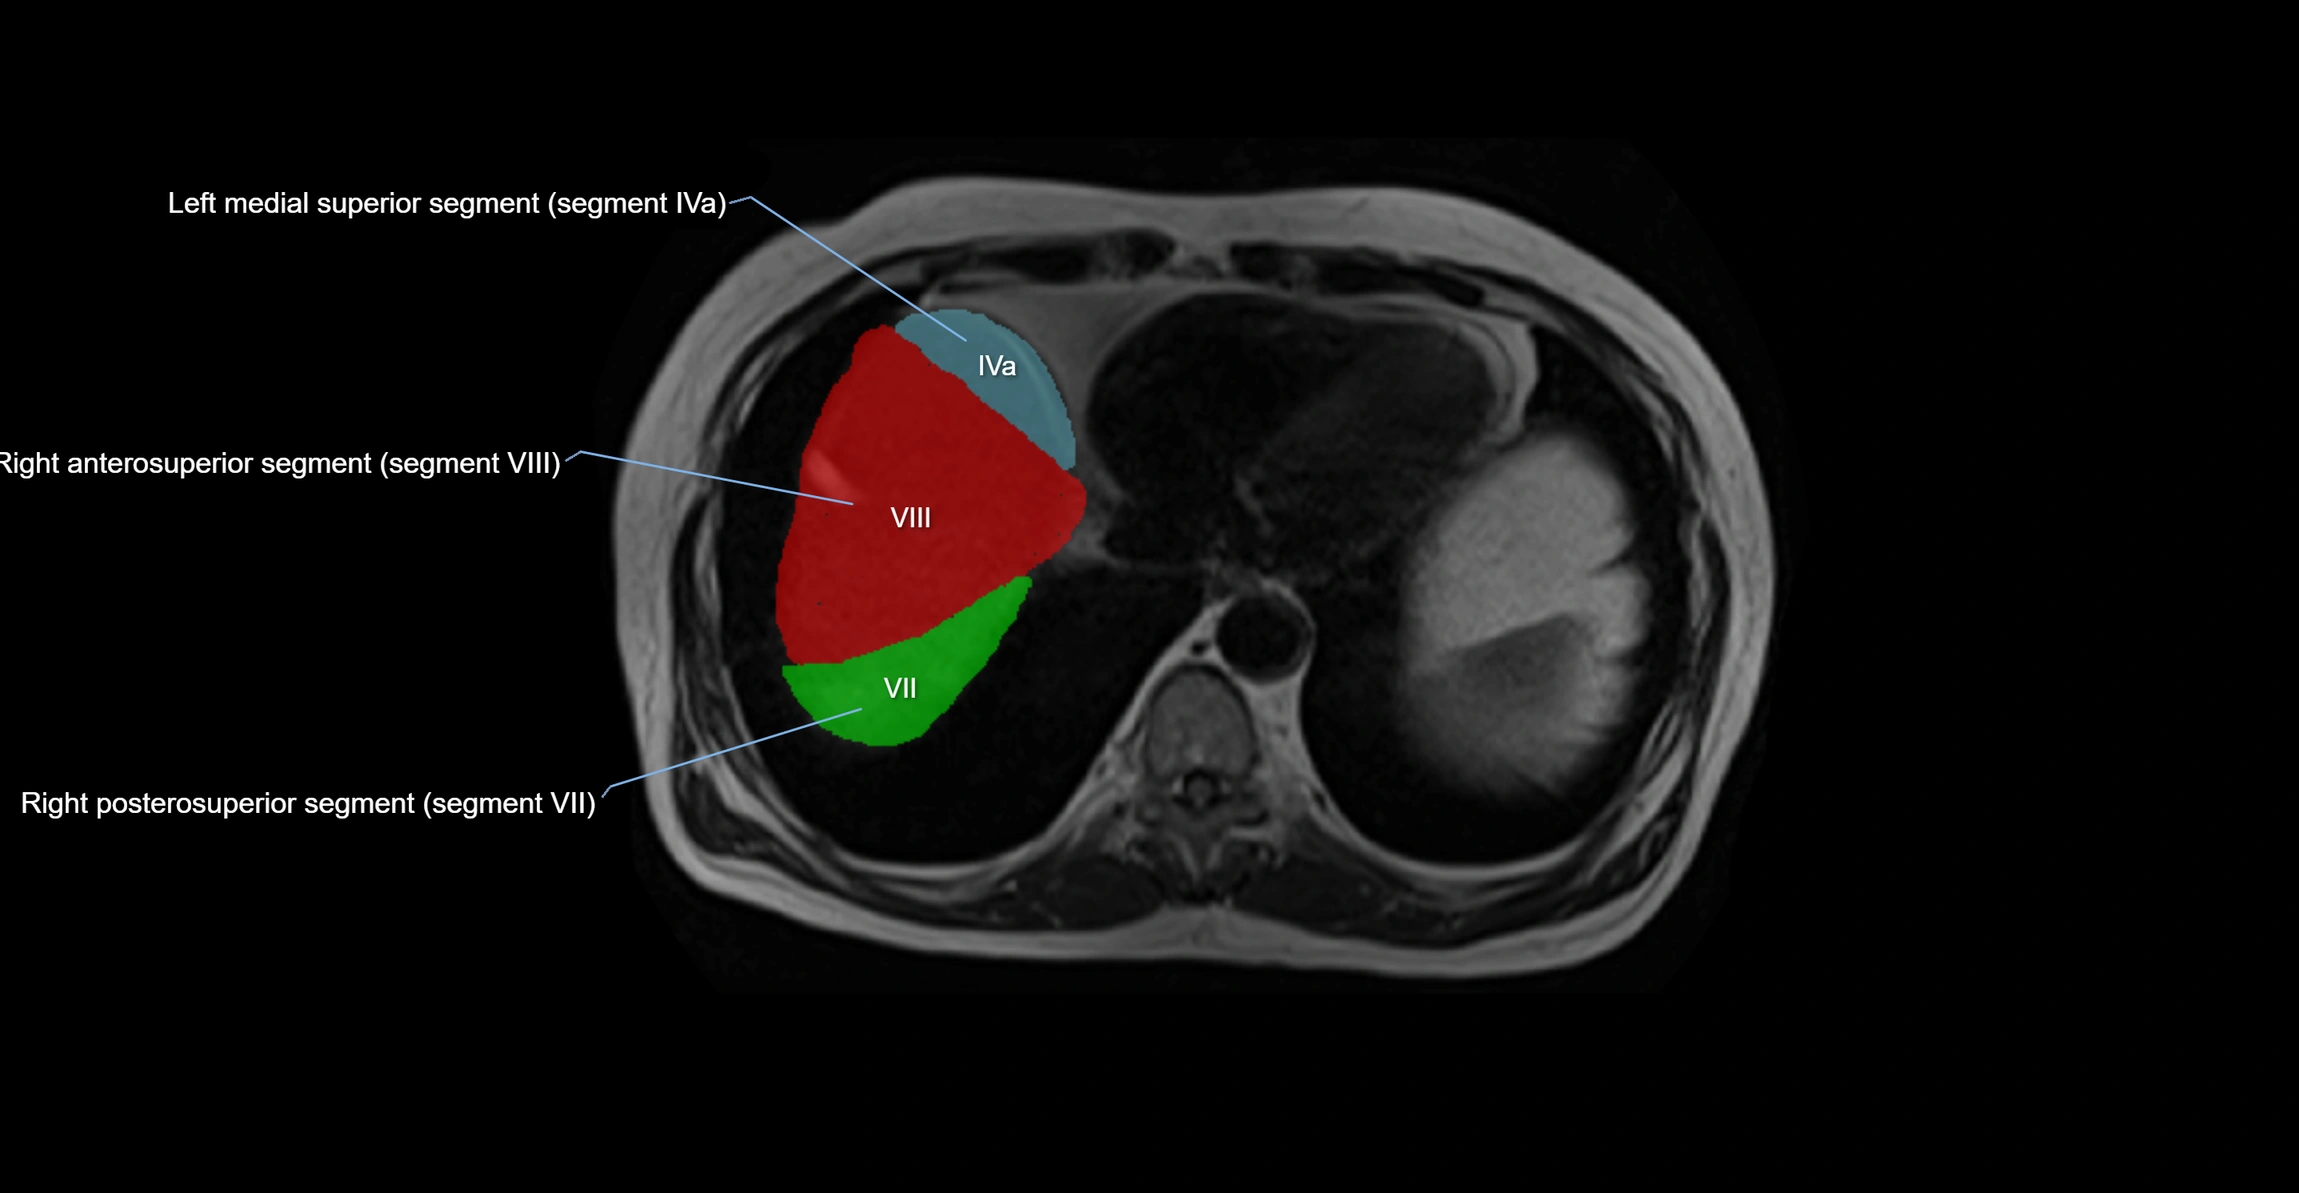

The caudate lobe of the liver is a distinct anatomical subdivision of the liver, designated as segment I in Couinaud’s classification. It lies on the posterior surface of the liver, between the fissure for the ligamentum venosum (left boundary) and the groove for the inferior vena cava (IVC) (right boundary). Superiorly, it is related to the posterior liver surface, and inferiorly it is separated from the left lobe by the porta hepatis.